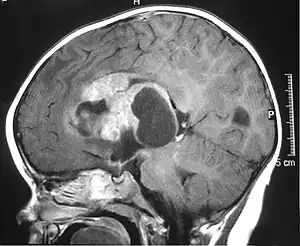

| MRI of an AT/RT | |

The initial diagnosis of a tumor is made with a radiographic study (MRI[22] or CT-). If CT was performed first, an MRI is usually performed as the images are often more detailed and may reveal previously undetected metastatic tumors in other locations of the brain. In addition, an MRI of the spine is usually performed. The AT/RT tumor often spreads to the spine. AT/RT is difficult to diagnose only from radiographic study; usually, a pathologist must perform a cytological or genetic analysis.

Appearance on radiologic exam

AT/RTs can occur at any sites within the CNS; however, about 60% are located in the posterior fossa or cerebellar area. The ASCO study showed 52% posterior fossa; 39% sPNET; 5% pineal; 2% spinal, and 2% multifocal.[3]

The tumors' appearance on CT and MRI are not specific, tending towards large size, calcifications, necrosis (tissue death), and hemorrhage (bleeding). Radiological studies alone cannot identify AT/RT; a pathologist almost always has to evaluate a brain tissue sample.

The increased cellularity of the tumor may make the appearance on an uncontrasted CT to have increased attenuation. Solid parts of the tumor often enhance with contrast MRI finding on T1 and T2 weighted images are variable. Precontrast T2 weighted images may show an isosignal or slightly hypersignal. Solid components of the tumor may enhance with contrast, but not always. MRI studies appear to be more able to pick up metastatic foci in other intracranial locations, as well as intraspinal locations.